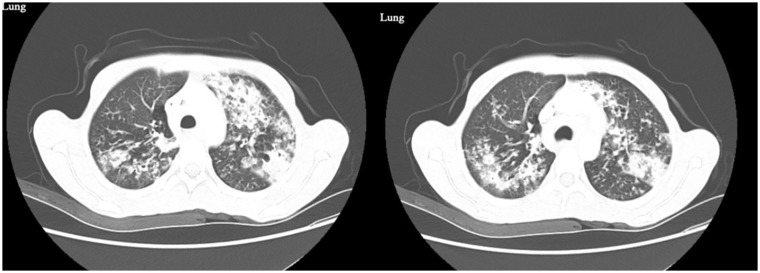

Cystic fibrosis (CF) is a genetic disorder typically diagnosed in early childhood, caused by mutations in the cystic fibrosis transmembrane conductance regulator gene, leading to thick mucus accumulation in the lungs, pancreas, and other organs. While most diagnoses occur in childhood, a growing number of cases are being identified in adulthood, presenting unique challenges for recognition and management. This case highlights a 37-year-old patient diagnosed with CF after presenting with chronic respiratory symptoms, and weight loss. Late diagnosis of CF remains rare but can delay appropriate treatment, potentially impacting long-term outcomes.